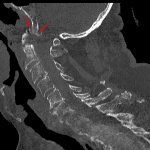

- Acute comminuted C1 burst fracture (Jefferson fracture) with fracture lines extending through the anterior arch, right lateral mass, and both lamina. On the right, the fracture extends into the C1-C2 articulation with associated asymmetric widening

- Comminuted impacted fracture of the basiocciput

- Anterior displacement of the anterior arch of C1 and odontoid process relative to the basion with mild associated mass effect on the nasopharynx

Acute comminuted C1 burst fracture (Jefferson fracture) with fracture lines extending through the anterior arch, right lateral mass, and both lamina. On the right, the fracture extends into the C1-C2 articulation with associated asymmetric widening. Lateral masses of C1 still articulate with the occipital condyles. Consider MRI to further assess for ligamentous injury.

Comminuted impacted fracture of the basiocciput.

Anterior displacement of the anterior arch of C1 and odontoid process relative to the basion with mild associated mass effect on the nasopharynx.